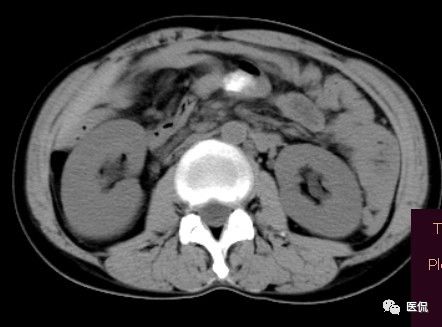

腹腔内残留的纱布在人体内引起渗出或液化坏死并纤维包裹形成异物性脓肿(纱布瘤)。纱布瘤的影像特点:圆形或卵圆形肿块,较大,有完整包膜,薄壁,较少的情况下为厚壁,边界较完整,增强后薄膜可以持续强化。不同时期的纱布瘤可以有不同表现:早期(10个月或半年内)多表现为蜂窝状;2~5年内一般表现为囊性飘带状;10~20年之后则为实性软组织密度,包膜钙化呈钙化网状结构。手术过程中残留在人体内的医用纱布所形成的肿瘤样病变。

纱布团遗留腹腔后,首先由大网膜及邻近肠管将其紧密粘连并包裹,自肠管与纱布团粘连处开始逐渐向周围扩展产生纤维结缔组织包膜直至完全包住纱布团,该包膜血管丰富,充血明显,随时间延长逐渐向纱布团网眼内生长,使包膜逐渐增厚。机体还通过在包膜内产生大量异物巨细胞来围歼异物纱线,使包膜内侧形成脓肿。当包膜完全形成后,肠管与纱布团的粘连变的疏松,此时纱布团具有了一定的活动度。

腹腔内遗留纱布团的影像学表现,以B超较具特征性,其主要表现为:腹腔或盆腔内特殊率减的黑色包块,后方伴有扇形衰减的声影,上窄下宽,好似一“黑色大布”,早期包块内含有不规则光团或光点,随时间延长有缩小或消失,为纱布团内气体。CT的优势在于早期常表现为软组织密度的肿块,其内可见多少不等的气泡,随时间的延长气泡逐渐被吸收减少至消失,增强扫描可见包膜不同程度强化而内容物无强化。熟悉其影像学表现,可在术前作出明确诊断。